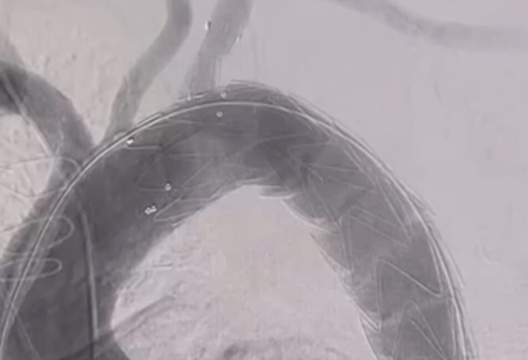

Однако эффективное и безопасное решение существует и активно внедряется во многих клиниках мира. Специалисты Центра Сердца UMC, следуя передовым тенденциям, впервые среди стран СНГ и Средней Азии применили новую технологию по малоинвазивной имплантации графта Castor. Данный стент-графт состоит из металлической каркаса, покрытого специальным полимером и укрепляющего ослабленную стенку аорты. Уникальность стента состоит в ее конструкции, при которой тело аорты и отходящая боковая ветвь сшиваются и раскрываются вместе при имплантации. Позиция стента и ее ветви фиксируется и адаптируется под анатомические особенности пациента, чтобы не нарушить кровоснабжение верхних конечностей.

Успешную имплантацию стент-графта Castor команда выполнила пациенту клиники с хронической аневризмой грудного отдела аорты с расслоением. Диагноз осложнялся сопутствующими заболеваниями и высоким артериальным давлением. До процедуры пациент испытывал давящие боли в груди, одышку, слабость.

«Новая технология отличается своей конструкцией тем, что имеет боковую ветвь для одновременного протезирования подключичной артерии. Ранее мы проделывали специальные отверстия при имплантации стент-графтов, чтобы не блокировать кровоток, и процедура занимала больше времени. Данный стент позволяет выполнить имплантацию намного быстрее, эффективнее и безопаснее», – поделился Марат Арипов, директор КАД интервенционной кардиологии и радиологии UMC.

Процедура имплантации стент-графта была выполнена малоинвазивным способом под общей анестезией, путем введения катетера через прокол в бедренной артерии. Пациент выписан с улучшенным самочувствием. Мастер-класс также посетили коллеги из клиник Алматы и Семея. Внедрение нового стент-графта позволит улучшить качество лечения и доступность лучших медицинских практик для пациентов, как в столице, так и в регионах.